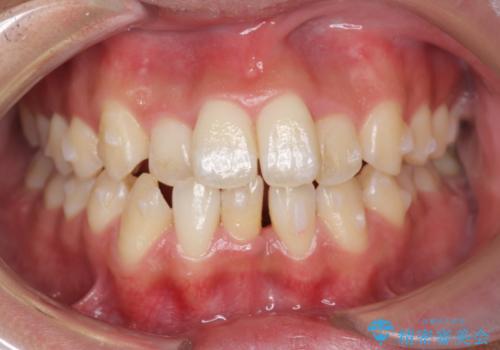

残りは全て天然歯になり、人工物の心配をしなくて済むようになりました。

治療も順調に進み、リファインメントも1回のみで済んでいます。

ブラックトライアングルも少なめで、短期間でしっかり並びました。

下の前歯の歯槽骨が一番薄く、歯肉退縮のリスクがあるため、今回のような1本抜歯も選択肢の一つです。

上の前歯のガタガタも、わずかに歯を削って並べていますので、出っ歯になったりしないようにしています。